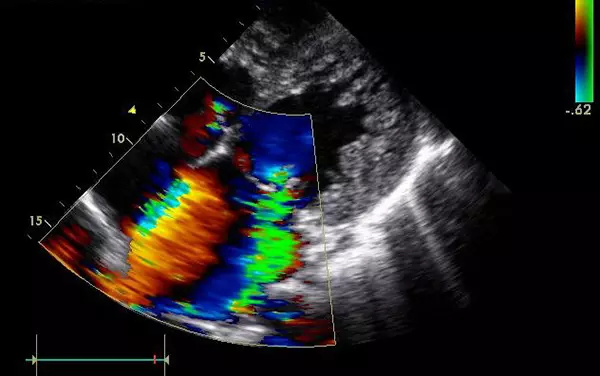

B超

B超的原理是用超聲波穿透人體,當(dāng)聲波遇到人體組織時(shí)會(huì)產(chǎn)生反射波,通過計(jì)算反射波成像。

優(yōu)點(diǎn):多方向觀察,實(shí)時(shí)成像。

缺點(diǎn):超聲受氣體干擾很大,對(duì)于腸道等含氣較多的器官,超聲診斷準(zhǔn)確率會(huì)降低,所以一般腸道檢查使用腸鏡。

5、心臟——排除冠心病用CT,看心功能用超聲